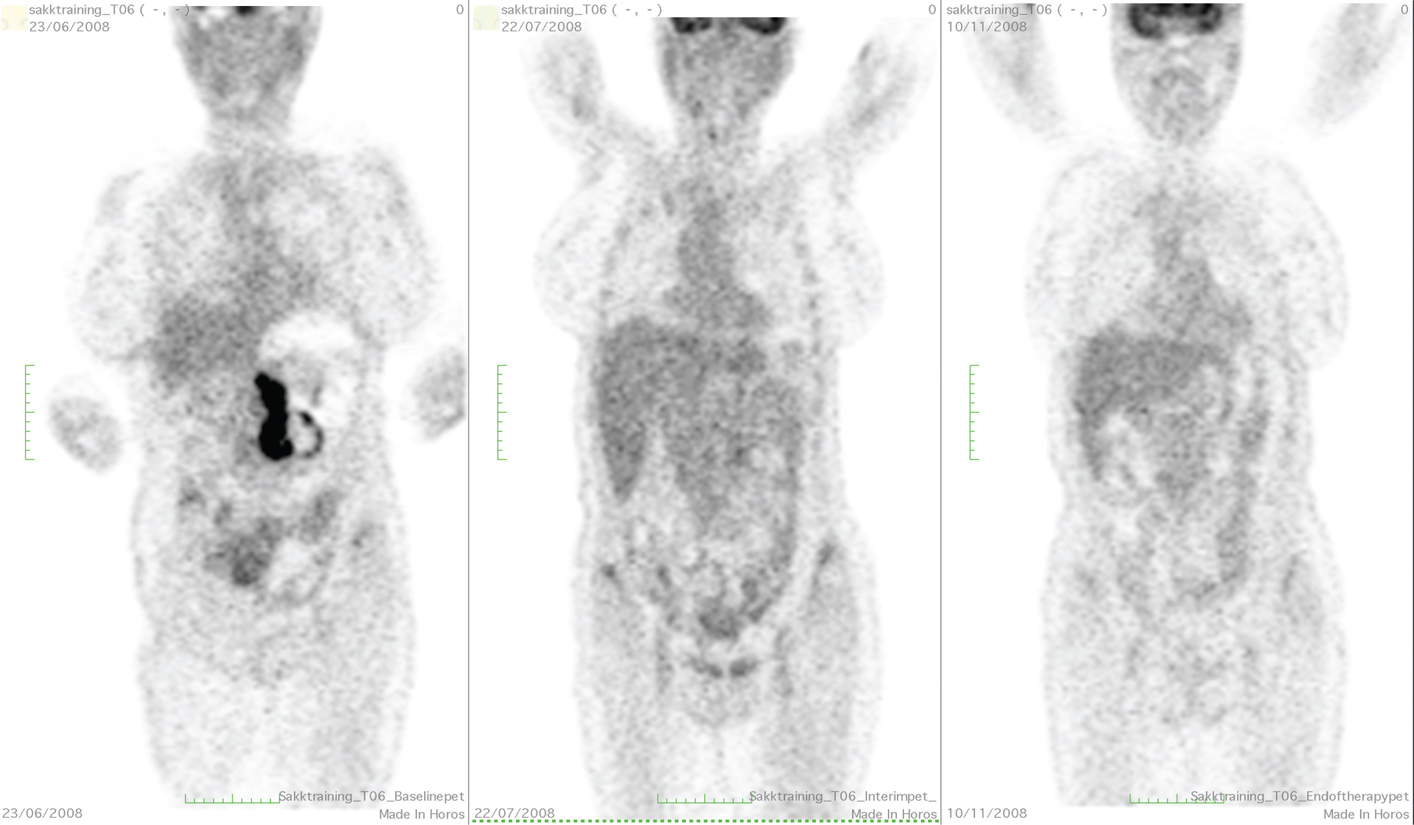

Based on the recent Lugano consensus recommendations for lymphoma staging, PET/CT in Ukraine is recommended as the “gold standard” for DLBCL patients staging and post-treatment assessment, with the following warning: PET/CT at baseline is “recommended”, but not “necessarily required’ in the absence of financial and technical support. For an interim assessment, we would rather provide CT scan, but iPET/CT imaging could be offered to the patient after 3–4 cycles of therapy in case of suspected disease progression. However, in some difficult clinical cases, an individualized approach outside guideline recommendations is required. For example, PET/CT is not recommended during follow-up, but it could be provided in the suspect of an impending relapse when a specific site of disease could be visualized only by PET/CT scan. An example of a patient with DLBCL treated with RCHOPx6 performing PET at different timepoints of the treatment––at baseline, after 2, and after 6 RCHOP cycles––is given in Figure 2.

Fig 2

Figure 2. An example of DLBCL lymphoma with PET/CT scan. San performed at baseline (left), after 2 (center), and after 6 R-CHOP cycles, at the end of therapy (right). The uptake in the mesenteric lesions decreased greatly after 2 cycles (while the CT lesion, not shown, had only a small variation) with an uptake comparable to the liver (complete metabolic response with a Deauville score 3) and substantially disappear after 6 cycles (complete metabolic response with a Deauville score 1).